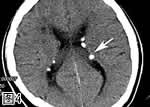

图4. 颅脑CT平扫,示双侧侧脑室室管膜下多发钙化性结节(箭号)